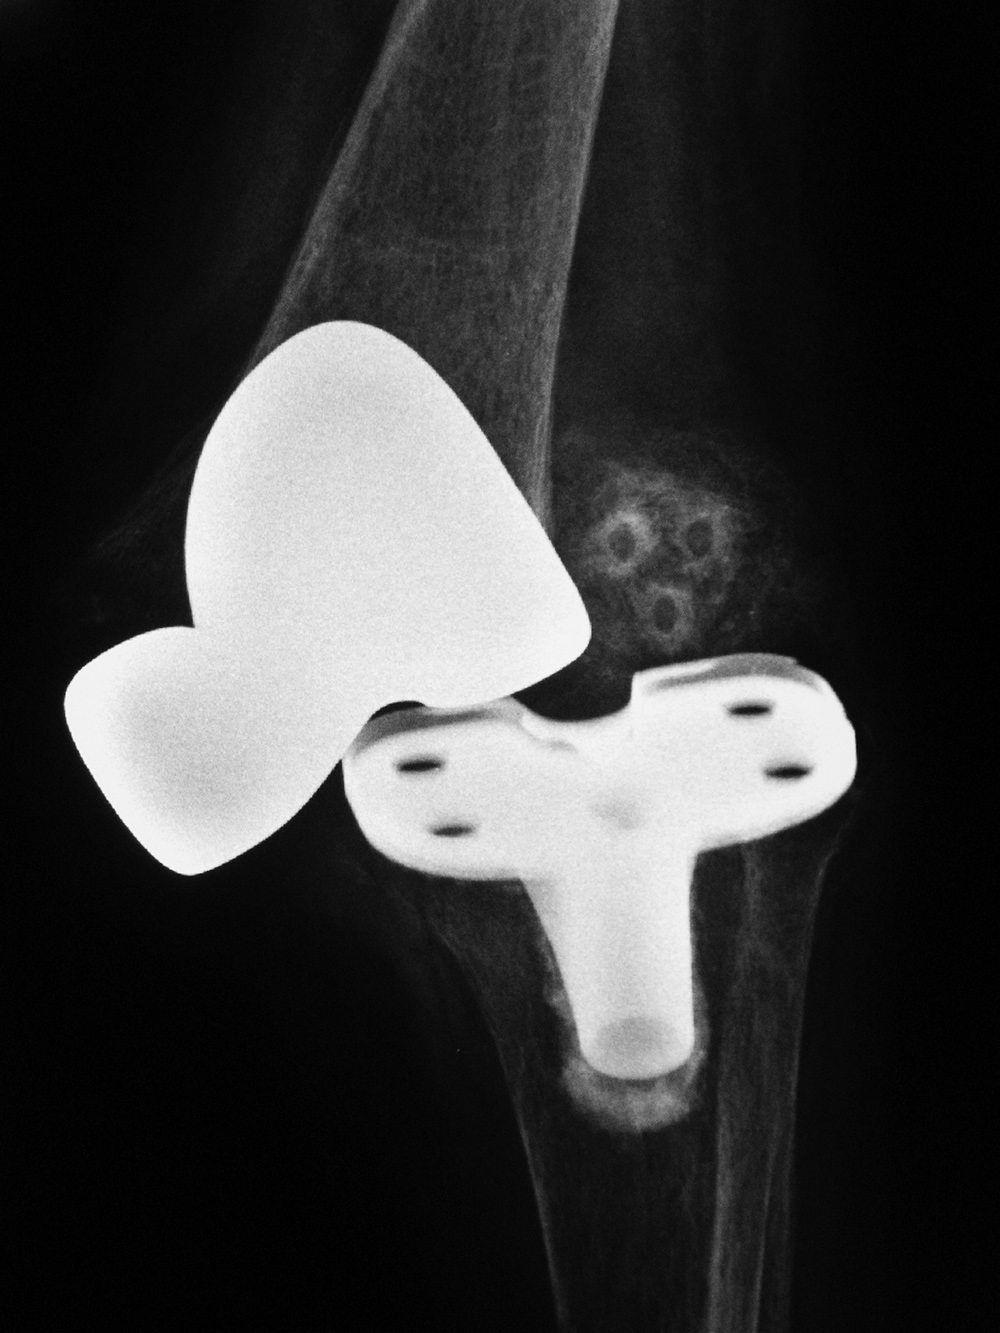

Rotating-hinge knee implant Rotating-hinge knee implant failure

Right knee revision arthroplasty Right knee revision implant Right knee revision implant failure Right knee revision implant failure

69 year-old man with revision of an infected right knee prosthesis (two left panels). A rotating-hinge knee implant was placed. Note the antibiotic beads about the medial aspect of the implant. The two fixation screws and wire are from prior surgery. There was implant failure with disruption of the implant six weeks later (two right panels).